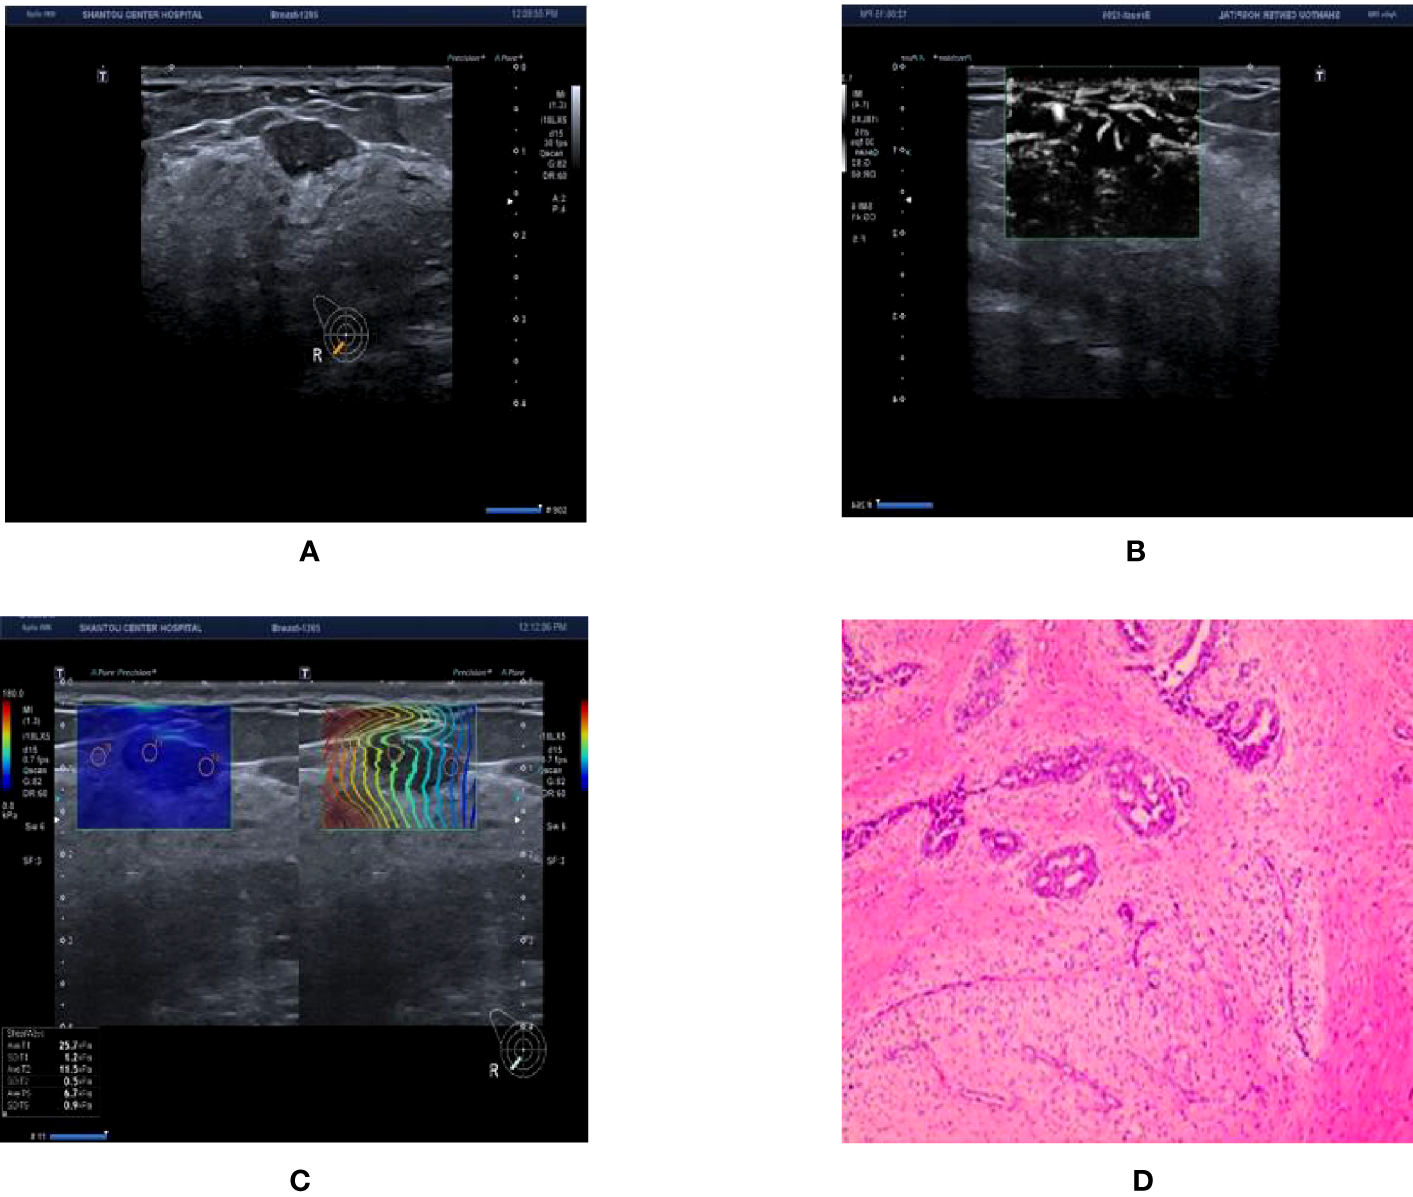

Figure 4

Ultrasound and pathological graphs. A 28-year-old female patient with a right breast nodule received ultrasound and pathological biopsy examinations. (A) A regular low-echo nodule was detected in the right outer and lower mammary quadrant, with parallel growth, lobed edges, even internal echo, and clear boundaries, BI-RADS 4a. (B) mSMI shows that microvessel morphology is dendritic subtype; BI-RADS grade was downgraded 1 level. (C) Shear wave elastic imaging: Emax is 25.7kPa < 77.25 kPa; BI-RADS classification was lowered or remained unaltered. (D) The nodule is a breast fibroadenoma based on pathological results.